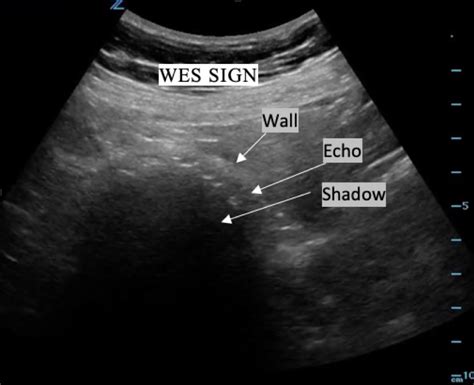

Wall Echo Shadow Sign. A curvilinear hyperechogenic line representing the gallbladder wall. There is no, or little anechoic bile visible surrounding the stones.

There is no, or little anechoic bile visible surrounding the stones. Web a “wall, echo, shadow” occurs when the gb wall contracts over gb stones so that the normal echo free space surrounding the stones is no longer visible. Adjacent bowel is mistaken for gallbladder. Web emphysematous cholecystitis is a rare form of acute cholecystitis where gallbladder wall necrosis causes gas formation in the lumen or wall. Start by placing the curvilinear probe in the subcostal region and slowly move your probe towards the right upper quadrant. Shadowing of air tends to be dirty, rather than the clean anechoic shadow of calcification. Wall echo shadow (wes) sign. A thin hypoechoic space representing a small amount of bile; Typically observed in patients with a contracted gallbladder around a. A curvilinear hyperechogenic line representing the near surface of gallstone (s)

It is a surgical emergency , due to the high mortality from gallbladder gangrene and perforation. A curvilinear hyperechogenic line representing the gallbladder wall; There is no, or little anechoic bile visible surrounding the stones. A thin hypoechoic space representing a small amount of bile; Consists of two parallel hyperechoenic lines (wall) separated by a hypoechoic space (echo), and distal shadowing (shadow) from the gallstone. Shadowing of air tends to be dirty, rather than the clean anechoic shadow of calcification. There should be a thin hypoechoic bile space between the gallbladder wall and the gallstone echo. Adjacent bowel is mistaken for gallbladder. Wes sign, referring the appearance of wall, echo, shadow in the setting of a contracted gallbladder containing acoustic shadowing gallstones. The hypoechoic area beneath the echogenic gall bladder wall and calculi represents interpostioned bile. Web a “wall, echo, shadow” occurs when the gb wall contracts over gb stones so that the normal echo free space surrounding the stones is no longer visible.